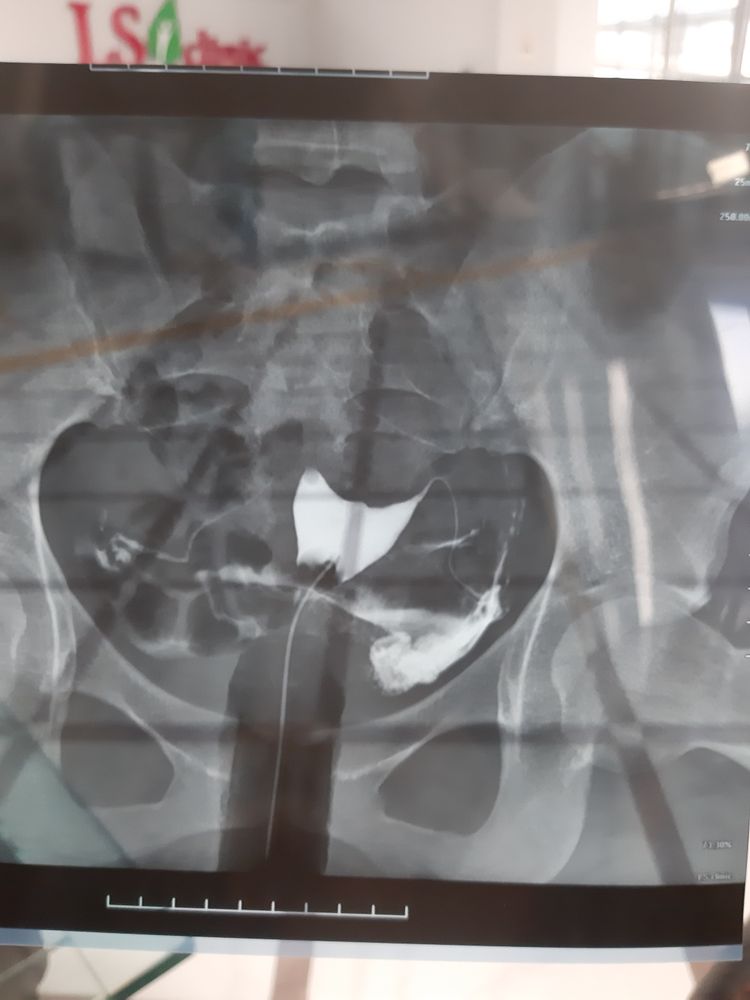

МСГ. С правой трубы контрастное вещ-во с трудом прошло

Стоит ли пить КОК и делать МСГ? Беременность в цикле МСГ